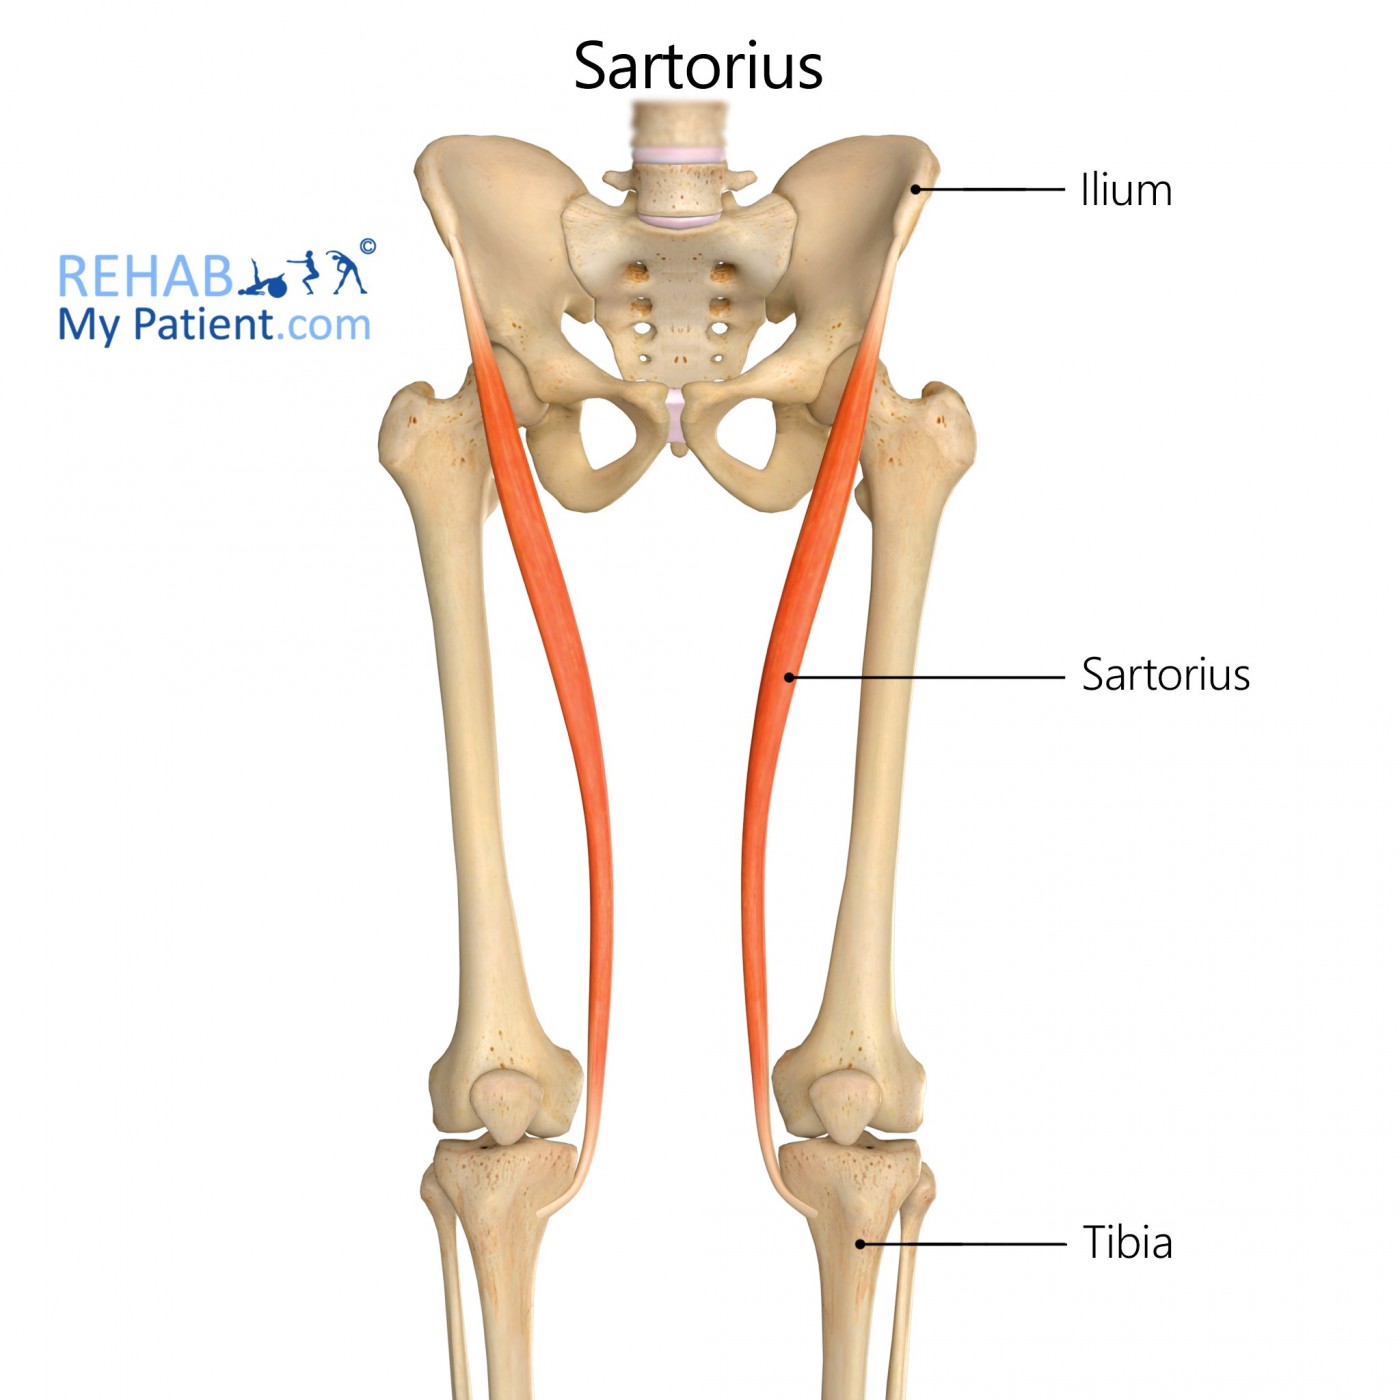

How does the sartorius muscle function during activities like getting in and out of a car?

what does sartorius muscle do Informational

- Why is the sartorius muscle sometimes referred to as the "tailor's muscle"?

- What are the potential benefits and risks of a sartorius muscle transfer?

- Can the sartorius muscle affect the patellar tracking?